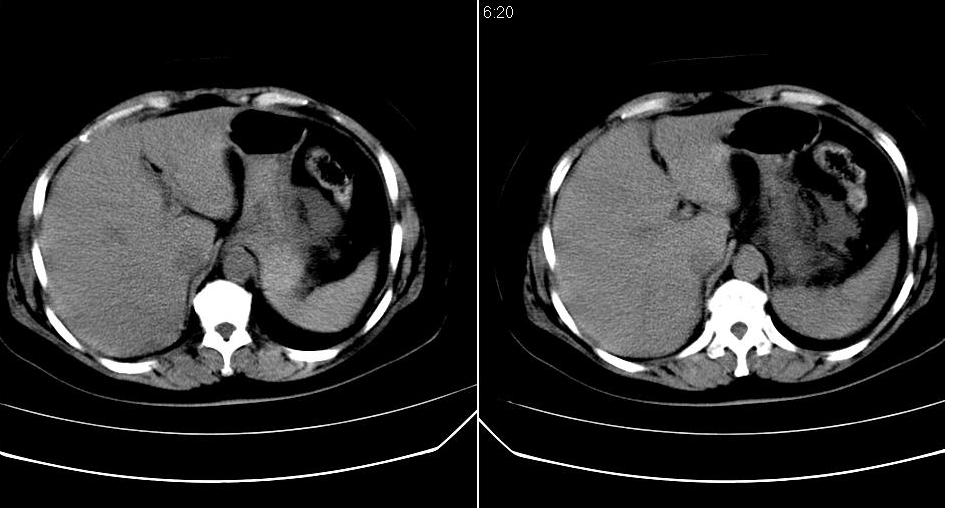

女 52岁,腹痛两天,无其它不适。

胆囊、胆总管结石,胰腺炎,少量腹水。

左肾周筋膜增厚,肾前间隙积液,胰腺肿大,胆囊结石,胰腺炎

慢性胆囊炎,胆囊结石,胆源性胰腺炎,少量腹水。

支持:左肾周筋膜增厚,肾前间隙积液,胰腺肿大,胆囊结石,胰腺炎。

左肾周筋膜增厚,肾前间隙积液,胰腺肿大,胆囊结石,胰腺炎。

胰头部囊状影是十二指肠。左侧肾前筋膜增厚、少量积液,胰腺增大,边缘模糊,支持胰腺炎。

2、胆源性胰腺炎,诊断依据:同1外+左肾周筋膜增厚,肾前间隙积液,胰腺肿大。